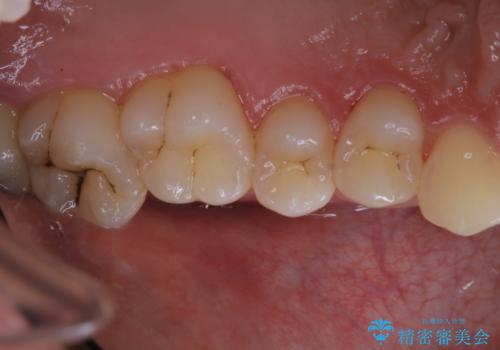

タバコによる着色をPMTCできれいな白い歯に

- タバコによる着色を綺麗にしたいとのことで来院されました。PMTC60分コースを行いました。

タバコに含まれているものの中で、タールというものが歯の黄ばみの原因です。その黄ばみなどを、無理に落とそうとしたりすると歯の表面に傷がついてしまったり余計に汚れがつきやすい状態になることがあります。